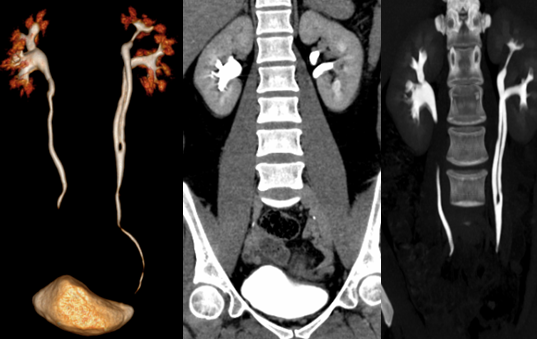

马蹄肾: 是融合肾中最常见的一种, 指两肾的上极或下极相融合,常见下极融合,融合的部分称峡部,由肾实质或结缔组织构成

IVP:两肾下极斜向内侧;两肾盂位置低,且靠近,旋转不良。可伴有肾盂积水